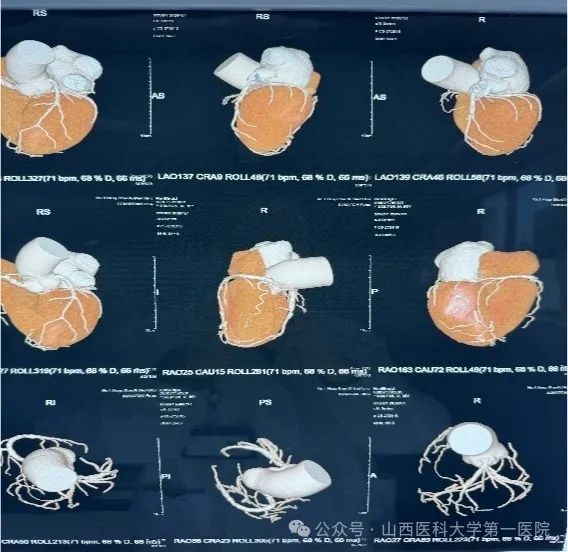

老人来自山西灵石,患慢性阻塞性肺病10年,因“胸憋气短加重7天”入住呼吸与危重症医学科,出院后又因“急性尿潴留,持续肉眼血尿”再次入住急诊医学中心,接诊医生给与留置尿管,持续膀胱冲洗。既往病史还包括:13年前因冠心病行冠状动脉支架置入术(3枚),后未复查(住院后复查发现仍有两支病变,最多狭窄80-90%),长期口服抗血小板药物,偶有背部不适,活动后明显气喘,长期卧床。前列腺核磁提示前列腺巨大,约109ml(正常人约20-30ml)。此前,患者就因反复出现急性尿潴留、血尿而四处求医,因身体状况差,无法耐受麻醉及长时间手术而选择药物治疗,但效果不明显,生活质量极差。